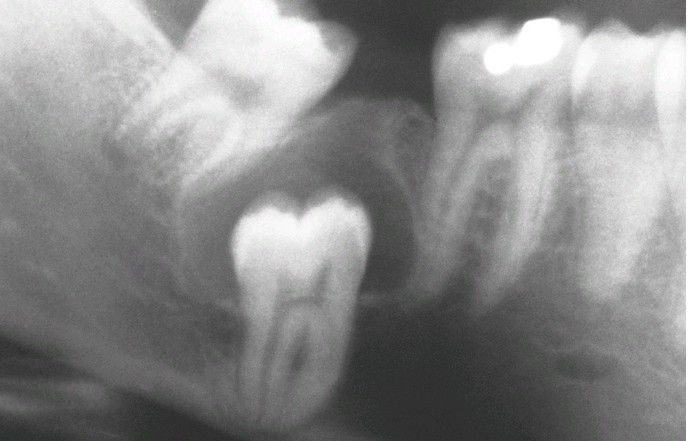

Dentigerous Cyst.

Central type showing the crown projecting into the cystic cavity